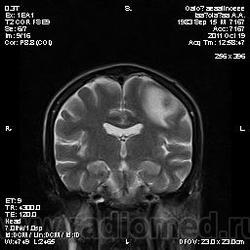

Молодой человек, жалуется только на головные боли и слабость в правой руке и ноге (около месяца).

Пациент полуасоциальный, нельзя исключить анамнез наркоманский....

ППН (включая ячейки пирамидок и сосцевидные отростки) тотально заполнены жидкостным компонентом...

Колеги, спасибо за высказывания. В данном случае про наркоманский анамнез указано не спроста... Есть мнение, что в этом лежит точка отсчета.... По поводу абсцесса и гематомы - не согласен; по поводу первого - нет соответствющей клиники, по поводу второго - не характерна локализация и сигнальные характеристики. Не буду томить общественность касательно собственного мнения. Есть две гипотезы, о которых думается в данном случае: прогрессирующая лейкоэнцефалопатия и новообразование... Но без контраста их не разрешить...